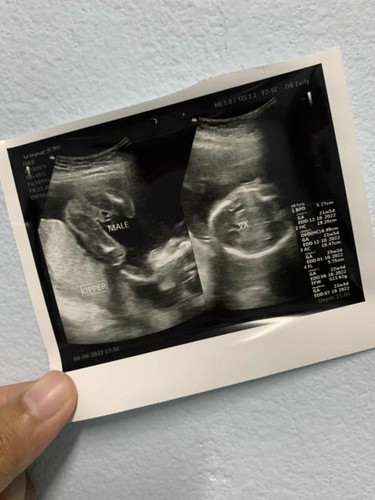

แม่ๆช่วยดูให้ทีคะ แบบนี้มีโอกาสเพศเปลี่ยนไหมค่ะ

ท้องแรกค่ะ ดูใบซาวด์ไม่ออกแล้วยังมีคนทักว่าได้ผู้หญิงตลอดเลยค่ะ

น่าจะชายแน่นอน100% เว้นแต่น้องจะเลือกเพศเองตอนโตจ้า